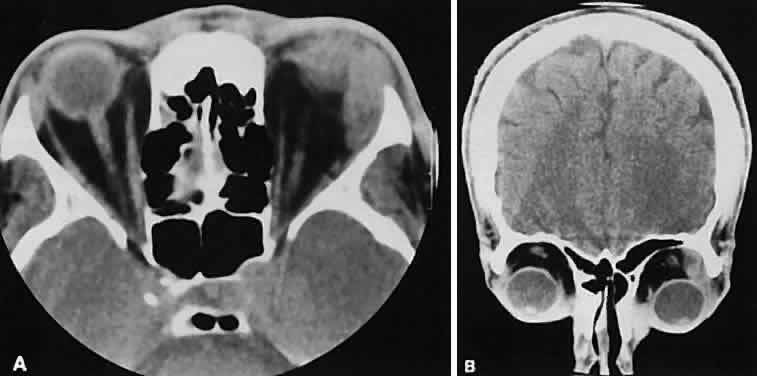

An appreciation for the various pathologic processes that affect the orbit is facilitated by an understanding of the normal orbital anatomy (Fig. 1). The orbit is a pyramid-shaped bony structure bounded inferiorly by the maxillary sinus, medially by the ethmoidal sinus, and superiorly by the frontal sinus. The sphenoidal sinus is situated posteriorly along the medial orbital wall and has a common wall with the optic canal. The lacrimal gland lies within its fossa located in the superior temporal aspect of the orbit and can be seen on both axial and coronal views.

Fig. 1. Normal anatomy. A. Axial scan through the plane of the optic nerve. Note the normal size of the horizontal rectus muscles and the undulating course of the optic nerve. B. Coronal view of the right orbit. The plane of section is slightly oblique to avoid dental artifacts and is immediately behind the right globe, which is partially volume averaged inferiorly. The arrow points to the optic nerve.